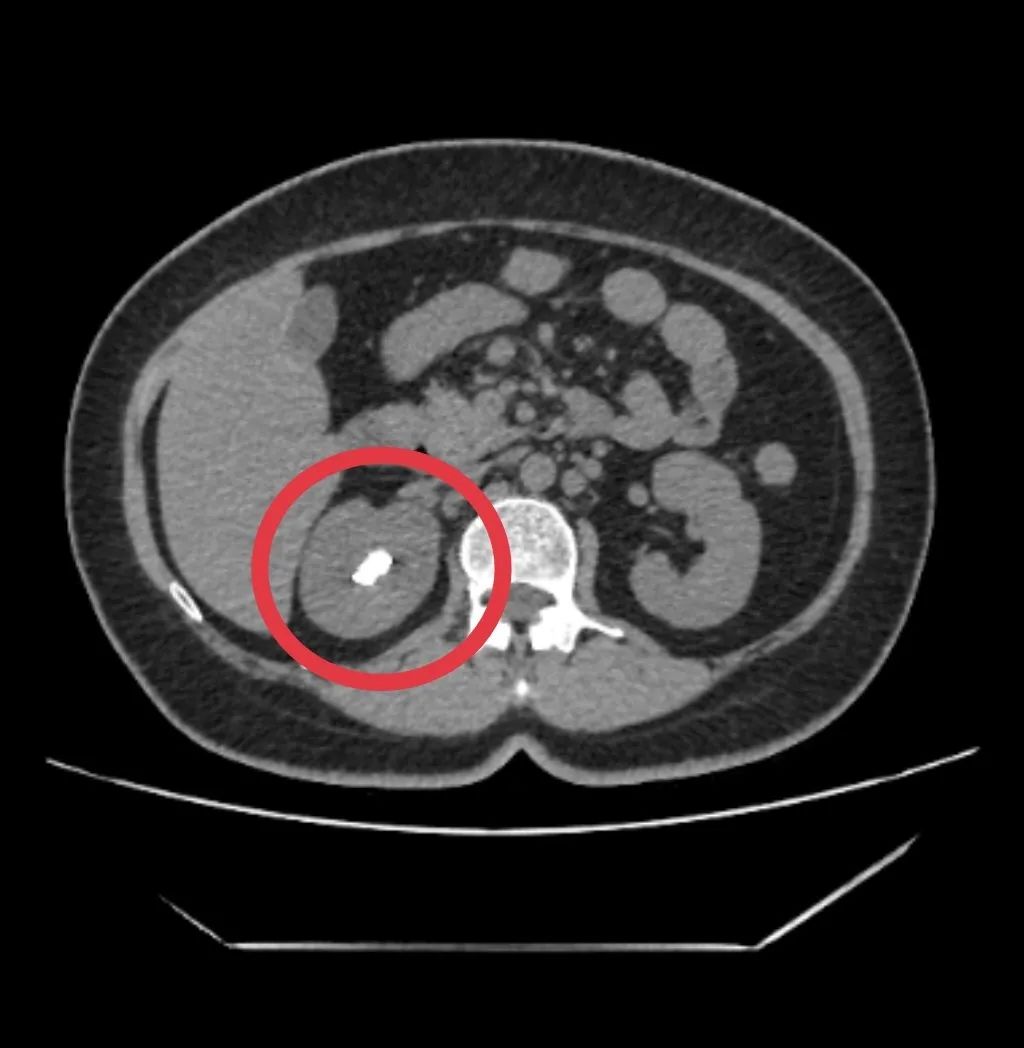

许女士(化名)的经历,为我们敲响了输尿管内支架规范管理的警钟。一年多前,她因右侧输尿管上段结石合并肾积水就诊,却恰逢早期妊娠无法手术,医生为其植入输尿管内支架以缓解梗阻。然而,因未按时返院更换,如今再次就医时,CT 检查显示支架上已附着大量结石,形态如同 「棒槌」—— 这正是支架长期留置引发的典型问题。

面对复杂情况,许女士来到了漳州第三医院泌尿一科,陈川聪主任带领团队制定了精准的手术方案:通过「经尿道膀胱结石钬激光碎石取石术」「经尿道右侧输尿管软镜联合钬激光碎石取石术」及「经尿道右侧输尿管内支架取出术」,分步骤处理病灶。术中可见,右侧双 J 管(输尿管内支架的常用类型)头端已被直径约 4.0 cm×3.0 cm 的膀胱结石完全覆盖,医生先将膀胱内结石击碎取出,再通过输尿管软镜深入肾盂,将附着在支架及肾盂内的结石彻底粉碎并吸出,最终成功取出所有结石和滞留的支架,手术过程顺利。

尿液中含有尿酸、草酸钙等结晶成分,支架表面的微小缝隙和粗糙结构会成为结晶沉积的「基地」。随着时间延长,结晶逐渐聚集形成结石,不仅会附着在支架表面,还可能包裹支架、堵塞管腔,甚至扩散至膀胱、肾盂,就像许女士的「棒槌状」结石一样,大幅增加后续治疗难度。